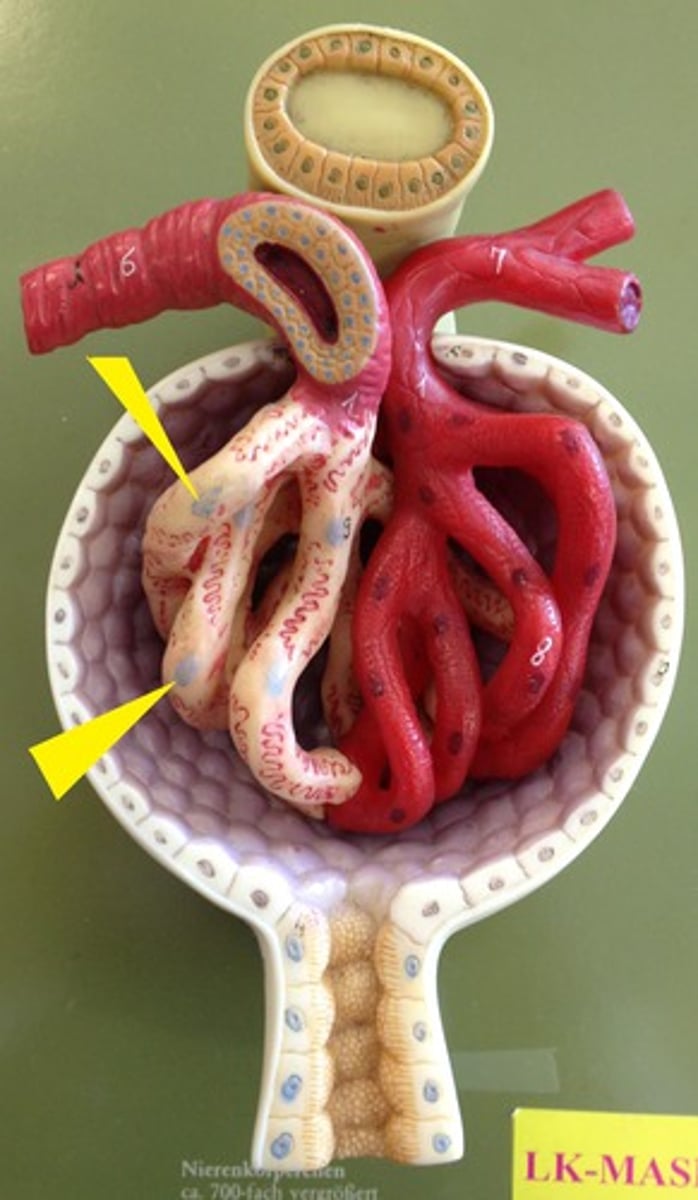

afferent arteriole

efferent arteriole

glomerulus

juxtaglomerular apparatus

Bowman's capsule / glomerular capsule

macula densa cells

cells

juxtaglomerular cells

cells

podocytes

cells

capsular space

the cavity

renal corpuscle

proximal convoluted tubule

distal convoluted tubule